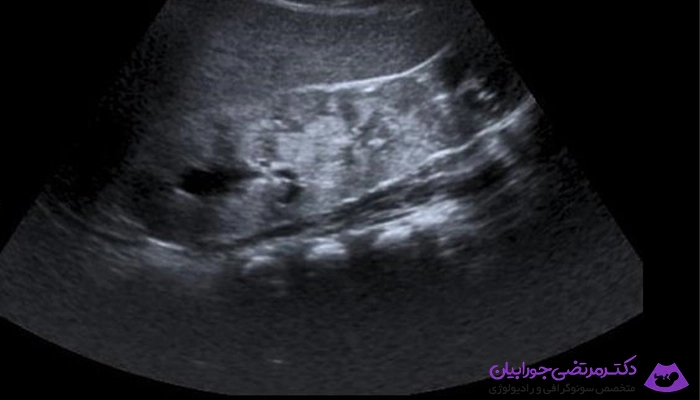

تصویر برداری با امواج اولتراسوند یا همان سونوگرافی شامل در معرض قرار دادن قسمتی از بدن با امواج صوتی با فرکانس بالا به منظور ایجاد تصاویر داخل بدن است.

امواج اولتراسوند به صورت Real-time گرفته می شود. لذا قادرند ساختمان و حرکت ارگان های داخلی بدن و همچنین جریان خون داخل عروق را نشان بدهند.

تصویری که همراه با گزارش سونوگرافی به بیمار ارائه می شود، در واقع تصویر یا تصاویر منتخبی از صدها تصویری است که متخصص تصویر برداری در حین انجام سونوگرافی بر روی مانیتور دستگاه مشاهده کرده است.

دکتر جورابیان جهت انجام سونوگرافی در اهواز از یک وسیله یا ابزار خاصی که روی اندام فرد قرار می دهد. امواج صوتی با فرکانس بالا که نمی توان با گوش آن ها را شنید به داخل بدن می تاباند. این امواج پس از برخورد به بافت های گوناگون بدن بازتابیده شده و امواجی که بازتاب شده است را به وسیله همان ابزار دوباره دریافت می شود. داخل بدن انسان از بافت های گوناگونی تشکیل شده است که قدرت آن ها در بازتابش امواج صوتی متغیر می باشد. برخی از آن ها امواج صوتی را بهتر و برخی کمتر منعکس می کنند. امواجی از بدن به وسیله یک کامپیوتر بررسی و ارزیابی می شوند به شکل یک تصویر دریافت می شوند.